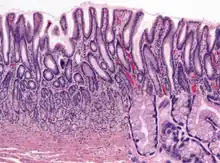

Gastric glands are mostly exocrine glands[2] and are all located beneath the gastric pits within the gastric mucosa—the mucous membrane of the stomach. The gastric mucosa is pitted with innumerable gastric pits which each house 3-5 gastric glands.[3][4] The cells of the exocrine glands are foveolar (mucus), chief cells, and parietal cells. The other type of gastric gland is the pyloric gland which is an endocrine gland that secretes the hormone gastrin produced by its G cells.

The fundic glands (or oxyntic glands), are found in the fundus and body of the stomach. They are simple almost straight tubes, two or more of which open into a single duct. Oxyntic means acid-secreting and they secrete hydrochloric acid (HCl) and intrinsic factor.[5]

There are millions of gastric pits in the gastric mucosa and their necessary narrowness determines the tubular form of the gastric gland. More than one tube allows for the accommodation of more than one cell type. The form of each gastric gland is similar; they are all described as having a neck region that is closest to the pit entrance, and basal regions on the lower parts of the tubes.[8] The epithelium from the gastric mucosa travels into the pit and at the neck the epithelial cells change to short columnar granular cells. These cells almost fill the tube and the remaining lumen is continued as a very fine channel.

Fundic glands found in the fundus and also in the body have another two cell types–gastric chief cells and parietal cells (oxyntic cells).

Human fundic glands (at fundus)